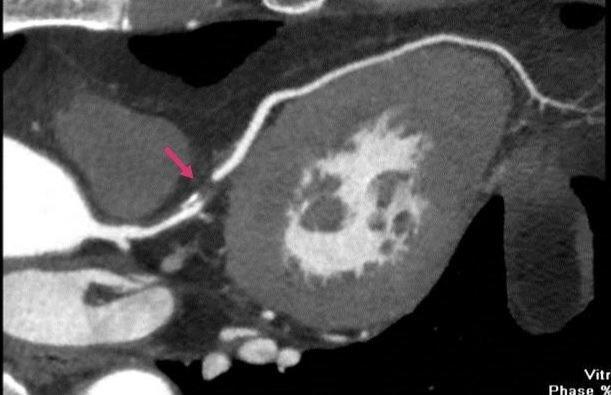

冠脉CT:在血管里注射碘造影剂,用CT来检查冠状动脉的情况,可以看冠状动脉有没有畸形、心肌桥、冠状动脉有没有斑块和狭窄。要注射碘造影剂,可能会出现造影剂肾病,对糖尿病合并肾功能异常的患者有一定限制。冠脉CT患者要注意要水化充分,以减少对肾脏的损害,促进造影剂的排泄。冠脉检查对心率有一定限制,一般要求70/分以下,心跳太快或不整齐会影响成像效果。

冠脉造影:通过手腕上的桡动脉,或者大腿根的股动脉穿刺把导管送到冠状动脉开口,注射碘造影剂,看冠状动脉的形态和血流。这种方法是目前诊断冠心病的“金标准”。对于糖尿病人来说,选在这种检查方法要同时做好放置支架的准备,当冠脉造影发现问题后要立即应用球囊扩张或置入支架开通冠脉,改善供血,这样可以检查和治疗同时进行,减少患者的痛苦和花费。这种方法属于微创手术,技术成熟,安全性很好,可迅速改善患者心肌的缺血症状。

箭头所指为闭塞的冠状动脉